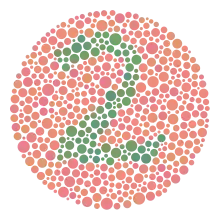

Le test se compose de trente-huit planches colorées, sur lesquelles un cercle constitué de points de différentes tailles et de couleurs légèrement différentes, lesquels sont apparemment disposés de manière aléatoire.

Les modèles de points se différencient par leurs couleurs et par un nombre.

Il permet de détecter toutes les déficiences dichromatiques sauf la tritanopie et la tritanomalie, d’ailleurs très rare. Une planche pseudo-isochromatique est constituée d’une mosaïque de points de couleurs différentes, disposés de façon apparemment aléatoire, au sein duquel apparaît une forme sur un fond. En réalité, les couleurs utilisées sont situées sur des axes de confusion colorés prédéterminés pour mettre en évidence un type de daltonisme précis. On utilise un nombre réduit de teintes. Chacune d’elles apparaît à plusieurs degrés de taille, de saturation et de luminosité. Ces degrés sont identiques pour chacune des couleurs représentées. Un ensemble de points reproduit une forme reconnaissable par l’unité de la teinte, mais, au sein de cette forme, on trouvera plusieurs saturations ou luminosités différentes de façon aléatoire. Le daltonien qui ne verra pas la couleur ne pourra pas non plus déchiffrer la forme par le seul fait d’une homogénéité de saturation ou de luminosité. À l’inverse, il existe des planches dans lesquelles cette homogénéité est utilisée pour faire percevoir des formes à des dichromates alors que les sujets normaux, trompés par des couleurs qui leur paraissent différentes, ne les percevront pas. Dans le daltonisme héréditaire, les lignes de confusion sont nettes et parfaitement déterminées. Cela permet une excellente fiabilité aux planches bien conçues, à la condition que les couleurs soient reproduites à l’impression. En revanche, par construction, une planche pseudo-isochromatique n’est pas adaptable et si l’axe de confusion du dichromate n’est pas rigoureusement celui qui a été prédéterminé, la planche sera jugée défectueuse. Cela se produit le plus souvent dans le cas d’une dyschromatopsie acquise. Chaque groupe de planches (tables) reproduites dans l’annexe (page 27 à 33) doit être interprété différemment.

Exemples de planches représentant successivement les numéros 12, 6, 2 (visible seulement en cas de déficience rouge-vert) et 42.

Ishihara Planche no 1.

Ishihara Planche no 1. Ishihara Planche no 11.